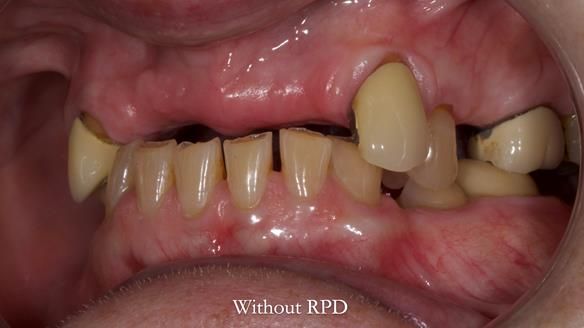

This is one of those cases that reminds me why I love removable prosthodontics. Pam was an absolute joy to treat — we were on the same page throughout. Her old upper flexible denture was loose, uncomfortable, and unaesthetic. We replaced it with a carefully designed metal-based upper partial denture/splint and new porcelain-bonded-to-zirconia (PBZ) crowns for the canines. The result is stable, comfortable, and natural-looking.

- Diagnosis and plan – Flexible upper denture ill-fitting with poor stability, retention, and appearance. Plan: metal-based upper partial denture/splint with lighter porcelain-bonded-to-zirconia crowns on UR3 and UL3.